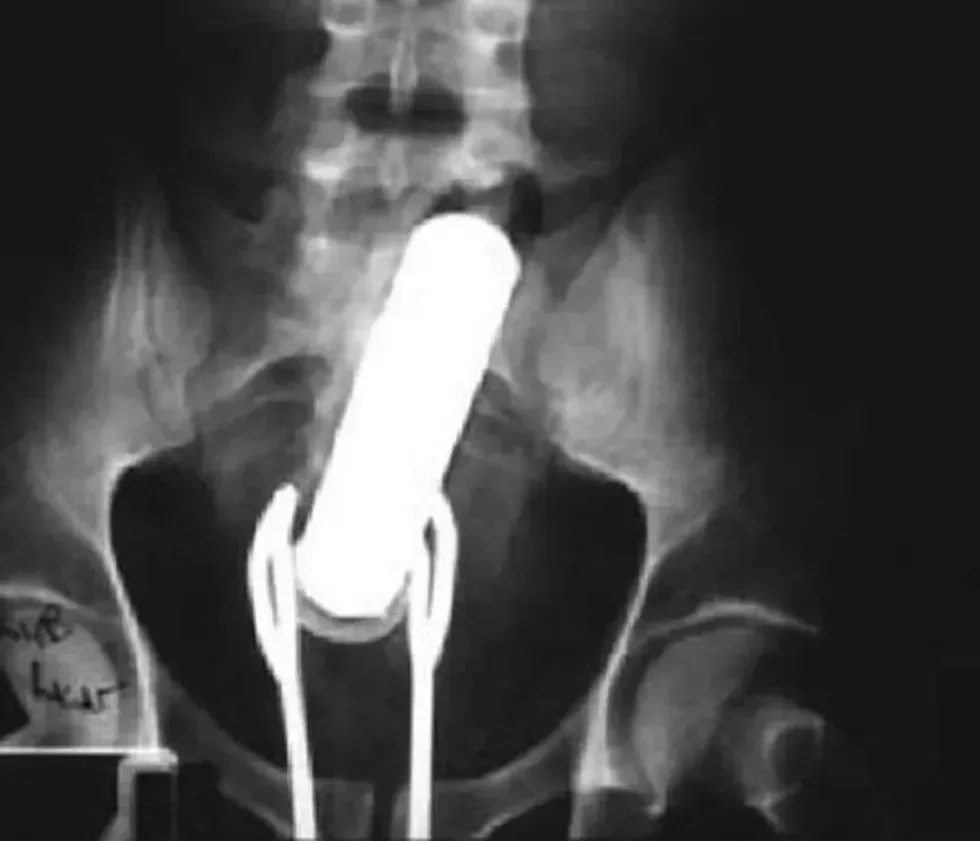

8. A flash light